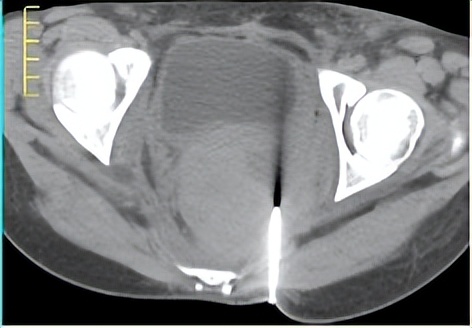

图2. CT引导下经皮穿刺瘤内注射免疫佐剂